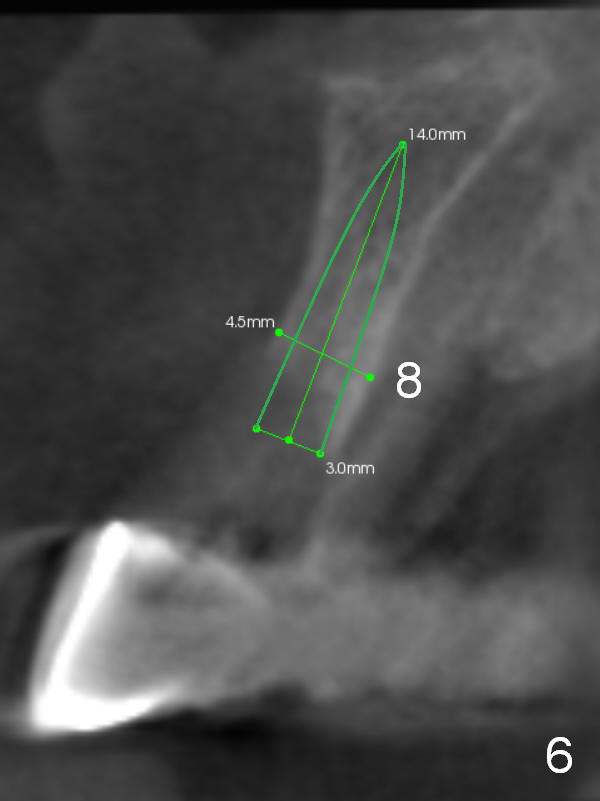

CT scan taken 10 days post immediate implant placement at #3, 4, and 10 shows that the edentulous area is narrow (Fig.1 (axial section), 2-6 (coronal sections; B: buccal)). In addition, the bone density is 100-200 Hounsfield units (Fig.2). Osteotomy should be underprep: 1.2 mm to the depth; 1.5 mm haft the depth. It appears that 2.5 or 3.0 mm 1-piece implants can be placed at #5,7 and 8 (Fig.3,5,6). Check buccopalatal trajectory after each step of osteotomy using surgical stent. Insert a 3 mm dummy implant tentatively. If it looks too wide for the ridge, use a 2.5 mm implant. If trajectory is off, use an angled one, especially at #7 (Fig.5).